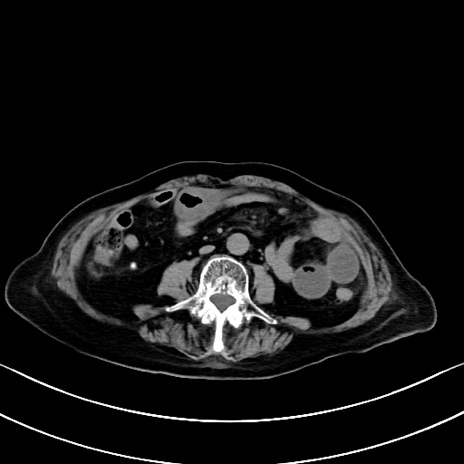

症例40(横断像)他院1日前

横断像

他院CT